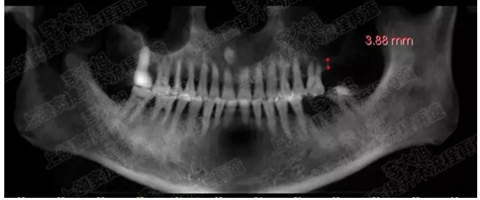

病例五

剩余不足1mm

112.png

提升10mm

113.png